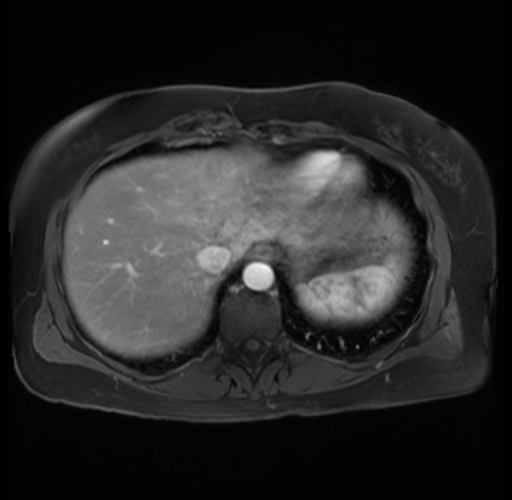

Imaging Analysis

Look through the patient's CT scan to identify any areas of concern for the necessary procedure.

Based on your CT findings, which issue(s) are present and would give reason for "planned slowing down moment(s)" in this case?